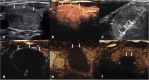

Methods: This retrospective study evaluated 194 non-functioning solid benign TNs of 103 patients. The TNs were categorized as small (≤5 ml), medium (5.1 to 13 ml), intermediate (13.1 to 30 ml) and large (over 30 ml) according to the initial volume of TNs before ablation. Clinical evaluation and contrast-enhanced ultrasound (CEUS) were carried out before ablation and the follow up at 1, 3, 6 months and every 6 months after ablation. All patients were asked to assess the cosmetic score (1-4 scores) and symptom score (0-10 scores) before ablation and every follow up after ablation.

Results: All patients underwent RFA without any major complications. The mean treatment sessions were 1.5 ± 0.6. 98 nodules required a single session (98/194, 50.5%), 87 required two sessions (87/194, 44.9%), 9 required three sessions (9/194, 4.6%). The average follow up months were 16.3 ± 5.6 (range, 6-24 months) and no nodule regrew in our study. After RFA treatment, the TNs volume significantly decreased (P < 0.001). The small group of nodules shrunk larger compared to the medium, intermediate and large groups (P < 0.001). Cosmetic signs and pressure symptoms were significantly improved, particularly in the intermediate and large groups (P < 0.05).